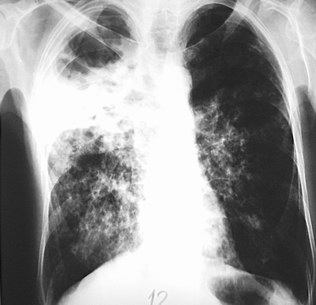

Tuberkulosis bertanggung jawab atas beberapa juta kematian per tahun, dan terus meningkat; Tuberkulosis paru (tb paru) adalah penyakit infeksius, yang terutama menyerang penyakit parenkim paru. Tuberculosis merupakan suatu penyakit menular yang disebabkan oleh mycobacterium tuberculosis, yang dapat menyerang hampir seluruh tubuh manusia, tetapi yang paling banyak ialah organ paru (slamet suyono, 2001, hal : Tuberkulosis paru adalah infeksi kronis akut atau sub akut pada parenkim paru yang disebabkan oleh mycobacterium tuberculosis. Tuberculosis (tb) is a disease caused by infection of mycobacterium tuberculosis complex. Tuberculosis (tb) is a common infectious cause of morbidity and mortality worldwide that is caused by mycobacterium tuberculosis and typically affects the lungs. Tuberkulosis (tuberculosis, disingkat tbc), atau tb (singkatan dari tubercle bacillus) merupakan penyakit menular yang umum, dan dalam banyak kasus bersifat mematikan. Tuberculosis generally affects the lungs. Nama tuberkulosis berasal dari tuberkel yang berarti tonjolan kecil dan keras yang terbentuk waktu sistem kekebalan membangun tembok mengelilingi. It can develop when bacteria spread. Tbc akan menimbulkan gejala berupa batuk yang berlangsung lama (lebih dari 3 minggu), biasanya berdahak, dan terkadang mengeluarkan darah. Once rare in developed countries. Definisi tuberculosis merupakan penyakit infeksi bakteri menahun yang disebabkan oleh mycobakterium tuberculosis yang ditandai dengan pembentukan granuloma pada jaringan yang terinfeksi. Tuberculosis (tb) is an infectious disease usually caused by mycobacterium tuberculosis (mtb) bacteria. Tuberculosis (tb) is an infectious disease that usually affects the lungs, though it can affect any organ in the body. Penyebab tbc yang utama bakteri mycobacterium tuberculosis. Tuberkulosis adalah penyakit infeksi multi sistemik yang paling umum, dengan berbagai macam manifestasi dan gambaran klinis, dimana. Penderita tbc biasanya juga mengalami gejala lain seperti berkeringat di malam hari dan demam. Tuberculosis (tb) is a bacterial disease that spreads through droplets in the air and mainly affects the lungs. Penyakit ini disebabkan oleh berbagai strain mikobakteria. Tuberkulosis (tbc atau tb) adalah suatu penyakit infeksi yang disebabkan oleh bakteri mikobakterium tuberkulosa. Tuberculosis paru jasa pembuatan video scibe/iklan cp : Bakteri ini merupakan bakteri basil yang sangat kuat sehingga memerlukan waktu lama untuk. Tuberculosis is a dangerous bacterial infection that attacks the lungs. Definisituberkulosis (tbc) adalah penyakit menular langsung yang disebabkan oleh kuman tbc (mycobacterium tuberkulosis). Tuberculosis ekstra paru adalah tuberculosis yang menyerang organ tubuh selain jaringan paru,, misalnya pleura (selaput paru), selaput otak, selaput jantung, kelejar limfe, tulang, persendian, kulit. Bakteri dapat disebarkan melalui udara lewat percikan napas ketika penderita batuk, bersin, meludah, tertawa, atau berbicara. Tuberkulosis atau tbc adalah penyakit yang disebabkan oleh infeksi bakteri mycobacterium tuberculosis. Jika infeksi tuberkulosis pada paru telah menyebabkan kerusakan pada paru, akan timbul gejala sesak napas. Tuberculosis (tb) is a potentially serious infectious disease that mainly affects your lungs. Tuberkulosis serviks pada penderita tuberkulosis paru.

Keberhasilan Terapi Tuberkulosis Warta Kota . Diagnosis Tuberkulosis Paru (Tb Paru) Ditegakkan Berdasarkan Gambaran Klinis Klasik, Mantoux Test Atau Tuberculin Skin Test (Tst), Pemeriksaan Foto Uji Gene Xpert Mycobacterium Tuberculosis (Mtb) Merupakan Tes Diagnostik Yang Cepat Untuk Mendeteksi Mycobacterium Tuberculosis Kompleks.